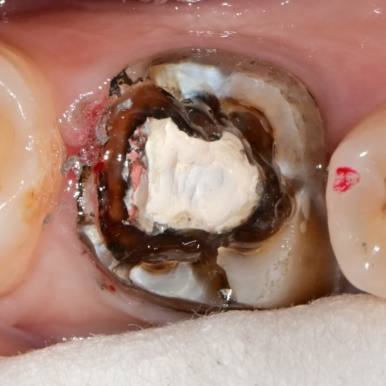

🔍 내부 상태 확인

- #46: 기존 보철 제거 시 아말감 코어 확인 → 내부 충치 확인

- #36: 보철 하부에서 크랙 라인 확인

➡ 감염된 부위는 완전 제거,

➡ 남은 치질은 레진 코어로 보강,

➡ 최종적으로 지르코니아 크라운으로 심미 보철 수복